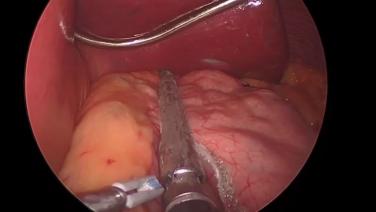

Laproscopic Sleeve Gastrectomy with ECHELON™+

Sleeve Gastrectomy with the ECHELON 3000 stapler and ECHELON Staple Line Reinforcement

Sleeve Gastrectomy Using the ECHELON™ 3000 stapler and ECHELON™ Staple Line Reinforcement with Dexter Turnquest, MD

Sleeve Gastrectomy with the ECHELON 3000 stapler, ECHELON Staple Line Reinforcement, and ENSEAL X1 Curved Jaw Tissue Sealer

Robotic Sleeve Gastrectomy Using the ECHELON 3000 Stapler and ECHELON Staple Line Reinforcement with Brian Binetti, MD